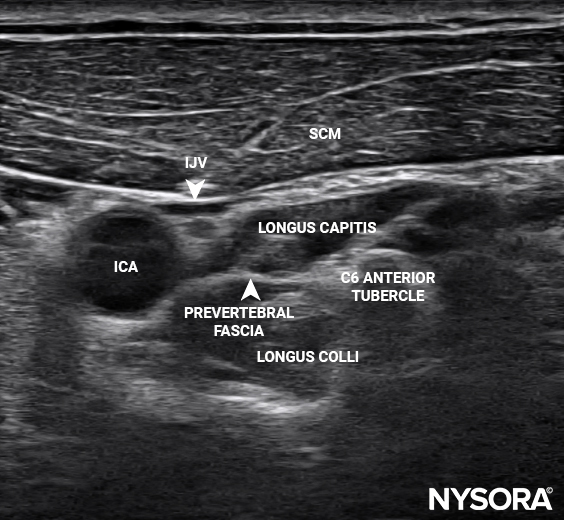

Detailed anatomical illustrations and ultrasound images.

NYSORA’s proprietary Reverse Ultrasound Anatomy simplifies the understanding of sonoanatomy.

Reverse Ultrasound Anatomy illustrations make sonoanatomy easier to understand and apply.

• High-resolution ultrasound images and anatomical illustrations

Yes. The app features detailed anatomical illustrations and NYSORA’s unique “reverse ultrasound anatomy” illustrations, helping you quickly recall sonographic patterns.

These are proprietary, revolutionary NYSORA educational tools. They take you from the ultrasound image to an illustrated anatomy view—and back again—via an interactive slider. This approach reinforces crucial anatomical knowledge and helps you master sonoanatomy patterns for effective ultrasound-guided pain procedures.